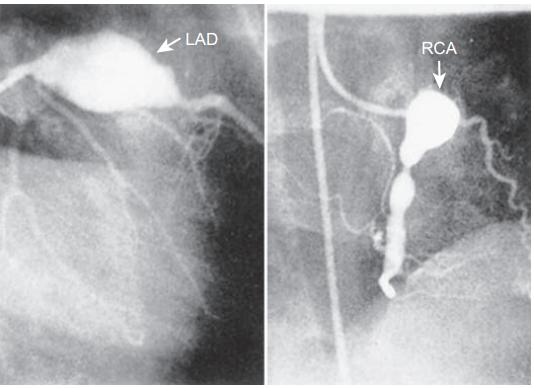

6岁儿童的川崎病的冠状动脉造影图,巨大冠状动脉瘤,参考6

CAA位于心外膜冠状动脉,最常见于左前降支近端和右冠状动脉近端。按发生频率依次为:左冠状动脉主干、冠状动脉回旋支、右冠状动脉远端,以及冠状动脉后降支在右冠状动脉上的起始处。CAA好发于分支处,这提示了剪切应力的病理学作用。

CAA可以呈囊状、梭状或膨胀状(弥漫性扩张且无节段性动脉瘤)。其形状和大小随时间推移而演变。例如,最初表现为膨胀状的动脉瘤可在数周内演变为节段状或珠状。